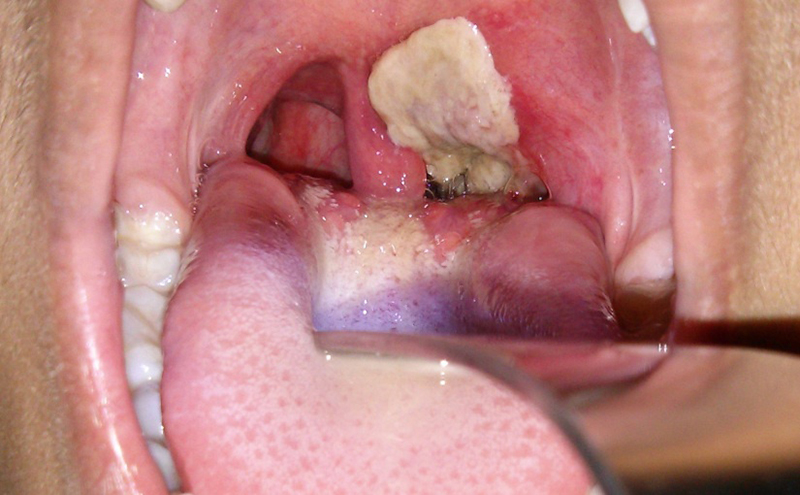

Tổng quan bệnh Bạch hầu    Bạch hầu là một tình trạng nhiễm vi khuẩn, có thể được ngăn ngừa bằng chủng ngừa. Tình trạng nhiễm trùng ở đường thở trên hay vùng mũi hầu tạo nên lớp màng xám, mà khi hiện diện tại vùng thanh quản hay khí quản,...